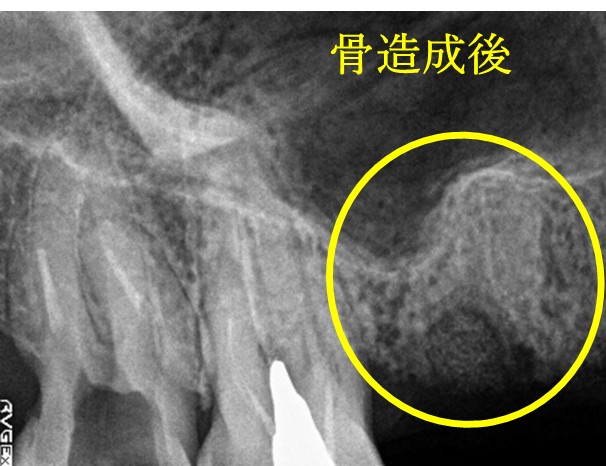

歯周病が進行し、保存することができず抜歯しました。大きく骨が欠損していましたので、骨造成後インプラントを埋入しました。

骨造成:¥55,000(税込)

インプラント1本:¥363,000(税込)

合計:¥418,000(税込)

Before

【抜歯後】

After